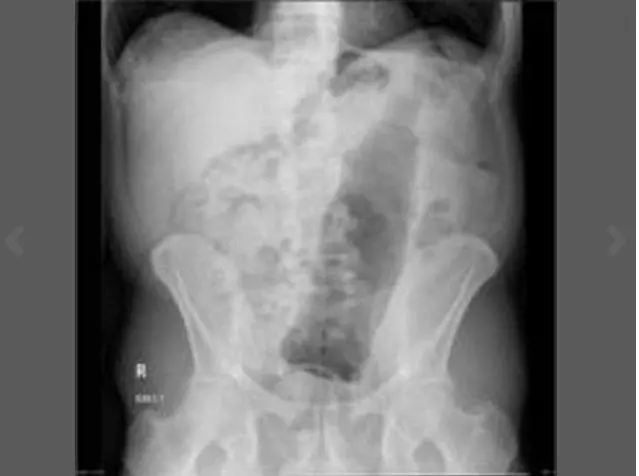

Pazze radiografie: gli oggetti che possono finire nel corpo umano

Oggetti bizzarri che hanno trovato la loro strada all'interno del corpo umano, e documentati grazie alle pazze radiografie raccolte dal dottor Frank Gaillard. Quest’ultimo ha fondato Radiopaedia.org, un sito collaborativo che raccoglie casi radiologici e articoli medici a tema.